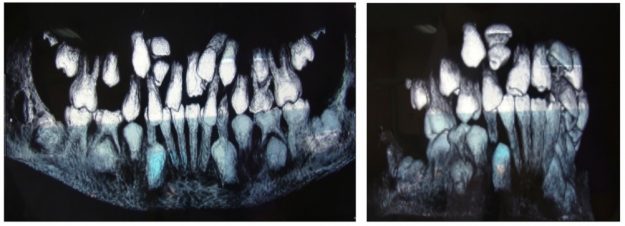

Лечение на свръхбройни зъби и ретенирани зъби Увеличеният брой зъби извън нормалния набор за човека (32 в постоянно съзъбие и съответно 20 за временно съзъбие) наричаме хиперодонтия. Те се формират и залагат от зъбната ламина, чрез разцепване на две и развитие на два зародиша. Свръхброините зъби могат да причинят различни нарушения, включително персистиране на временните…